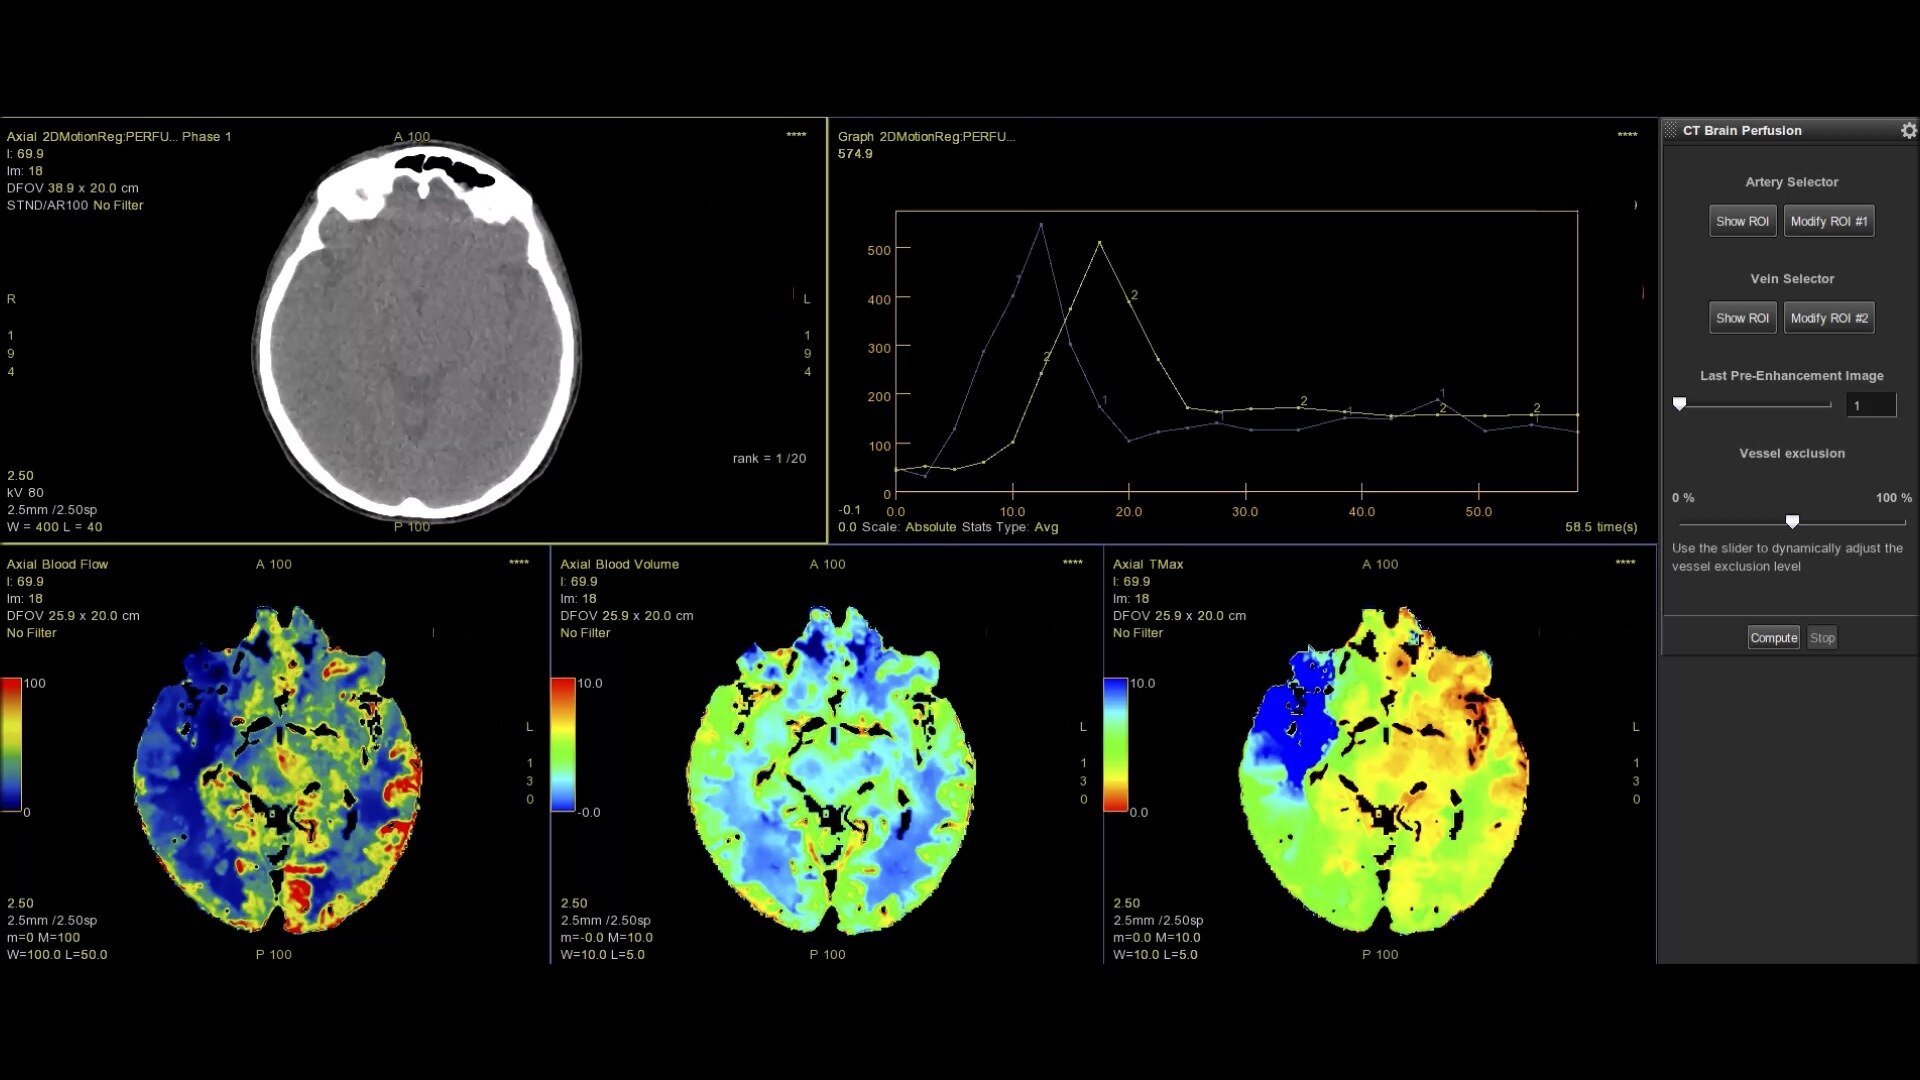

• Fully integrated with CT Perfusion 4D for visualization of perfusion functional maps³

• Deep Learning brain ventricle segmentation to prevent ventricular matter inclusion in quantitative results and improve visual inspection of the maps

• Automated computation of the functional maps